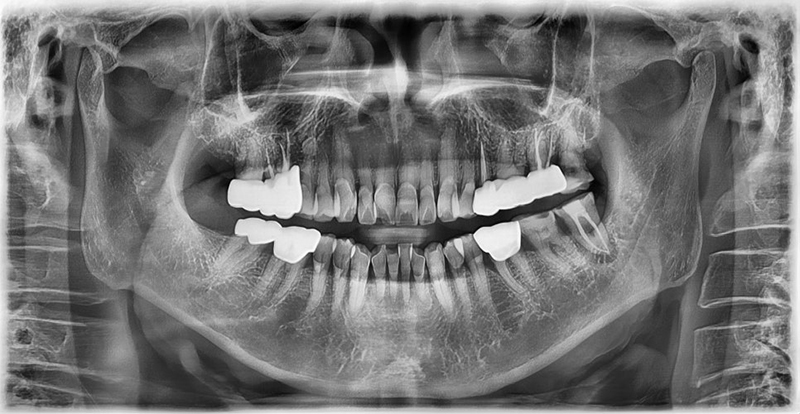

Case 1: 76-year-old male, diabetes (HbA1c 6.5%)

The patient visited us due to discomfort in the lower right molar. Although he had diabetes, his HbA1c was well controlled at 6.5%. The tooth had a root fracture and required extraction.

During anesthesia, his blood sugar temporarily spiked due to stress, so we monitored his glucose every 10 minutes until it stabilized below 200 mg/dL. After stabilization, extraction was completed safely.

One month later, we placed the implant, and the patient reported no discomfort.

After three months, the implant prosthesis was successfully delivered.